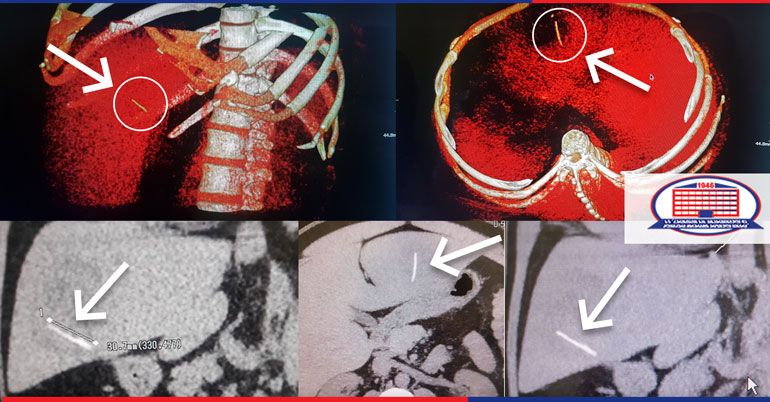

He complained about the dull pain in the right upper quadrant of the abdomen, had a high fever. On physical examination, the patient did not show the symptoms of acute abdomen, but the group of surgeons decided to do the abdominal cavity CT (computed tomography). The study was conducted with the CT machine Toshiba aquilion RXL, which is a leader in its class. The liver abscess has been found. It should be noted that the radiologist of the National Center of Surgery, Vasil Gergedava, noticed a foreign body in the abscess cavity.

An urgent surgery - laparotomy, draining of the abscess, was performed, the abdominal cavity was checked for hepatogastric fistula, and surgeons took a large piece of fish bone out of the abscess cavity. The surgery was performed by Gigo Pichkhaia and Shota Dzagania, surgeons of our clinic.